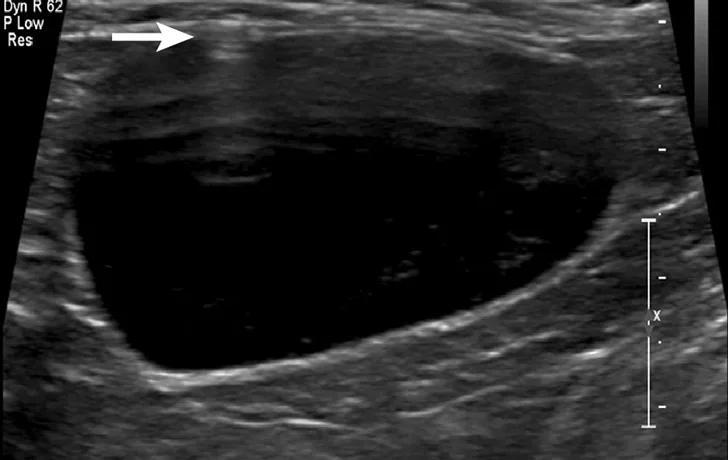

Cystocentesis is often performed with ultrasonographic guidance, although this is not required (ie, blind cystocentesis). Using ultrasonography can help direct visualization of the needle in the urinary bladder lumen, avoiding iatrogenic damage of surrounding structures (Figure 1). The relative size of the bladder, echogenicity of its contents, and any obvious structural abnormalities can also be observed. A primary advantage of blind cystocentesis is that it does not require special equipment. Cystocentesis can be challenging to perform in patients that have abdominal effusion and should be performed with ultrasonographic guidance in such cases.

FIGURE 1

Ultrasonographic image showing the cranial aspect of the urinary bladder (A), identified just before ultrasound-guided cystocentesis. It is important to adjust the depth of the image so that the urinary bladder is focused and to consider the depth of the urinary bladder using a machine scale that should be present on the ultrasound screen; in smaller patients the needle may only be partially inserted and not reach the hub (B; arrow).